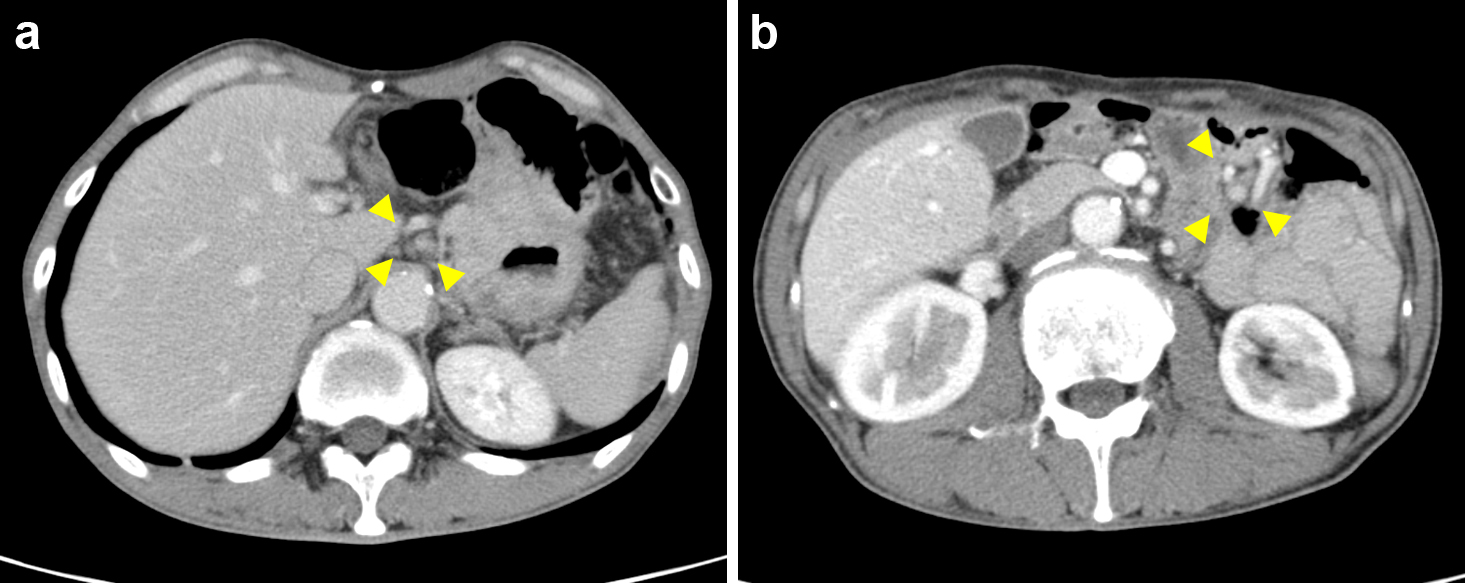

腹部造影CT所見:残胃全体に造影効果を受ける壁肥厚を認めた(Fig. 2a).腹腔動脈周囲および空腸動脈周囲に転移を疑うリンパ節を複数個認めた(Fig. 2b).その他明らかな遠隔転移は認めなかった.

Enhanced CT scan revealed wall thickening of the whole remnant stomach (a), swollen celiac lymph node (a, arrowheads), and jejunal lymph node (b, arrowheads).